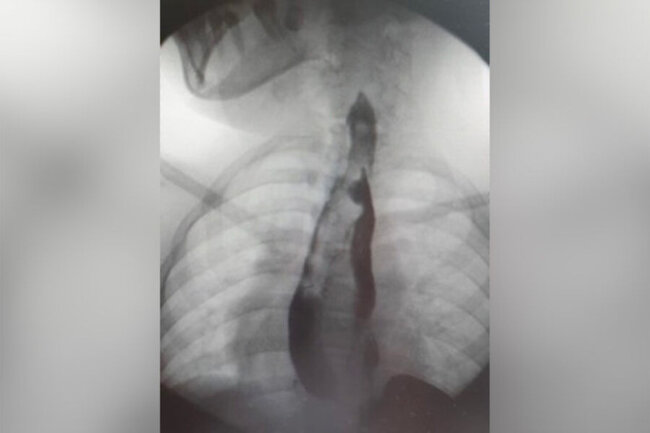

Rusiya Uşaq Klinik Xəstəxanasının cərrahları qarnı və yemək borusu qoşa olan Yakutiyadan olan məktəbli qızı əməliyyat ediblər. BİG.AZ bildirir ki, 14 yaşlı məktəbli qız qarın nahiyəsində vaxtaşırı ağrılardan şikayətləndiyi üçün ailə yaşadıqları yer üzrə klinikaya müraciət edib. Müayinə zamanı nadir bi